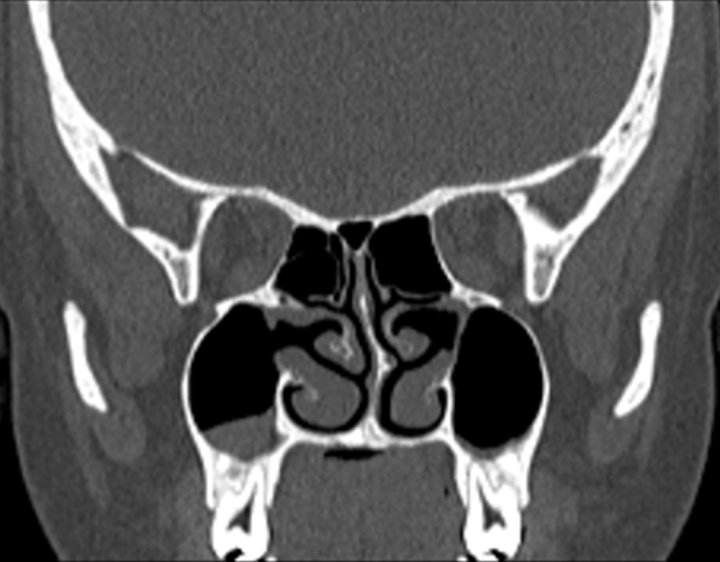

Click any image for labels.